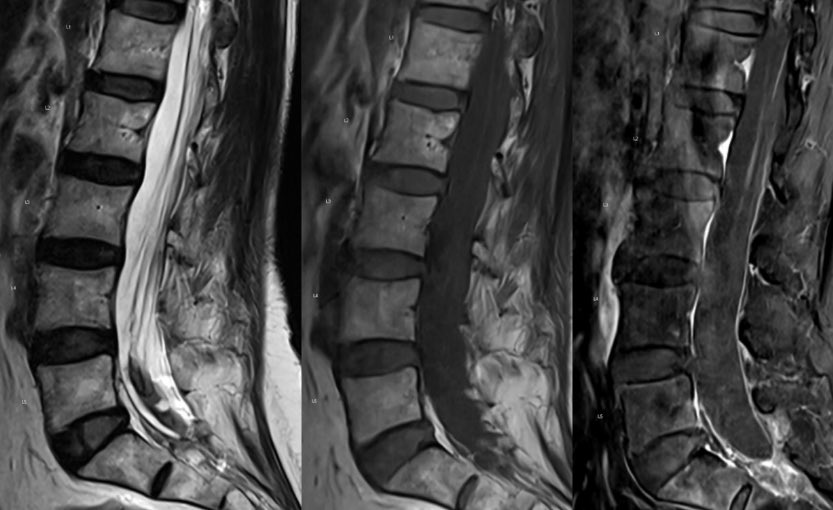

Important pitfalls: absence of obvious flow voids on MRI does not exclude the diagnosis. CSF is often abnormal (elevated RBCs protein common), but pleocytosis is uncommon.

Any unexplained thoracic myelopathy extending to the conus should prompt a thorough evaluation for a spinal dural AV fistula.